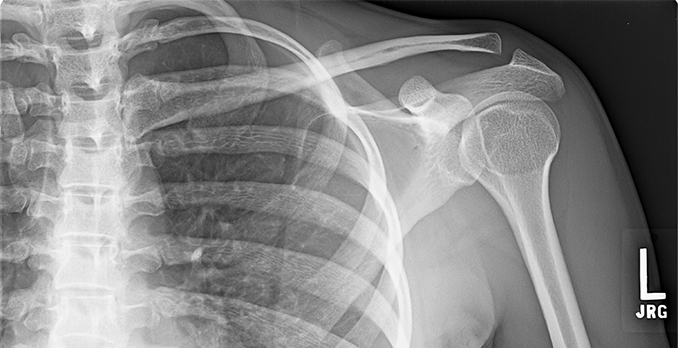

There is significant upward translation of the clavicle leading to a step deformity in a grade 3 ac joint injury. We conducted a survey among upper limb surgeons in the united kingdom to review commonly accepted practise. Grade 3 ac joint injury:

A Step Deformity May Be Apparent With Grade 3, 4 & 5 Injuries.

This is usually the result of years of degeneration or “wear and tear” of the joint and is common. Immediate ac joint injury physio will work to assess the severity of the injury and whether any other structures are involved. In a type iii sprain of the the ac joint, the ac ligaments and coracoclavicular ligaments are torn, with 100% ac joint dislocation.

Widening of the acromioclavicular joint. Although nonoperative treatment is considered the standard of care for the treatment of grade i and ii acromioclavicular (ac) joint injuries, the treatment of grade iii injuries is controversial. Depending on the grade of injury, most patients heal within 2 to 3 months without surgical intervention.